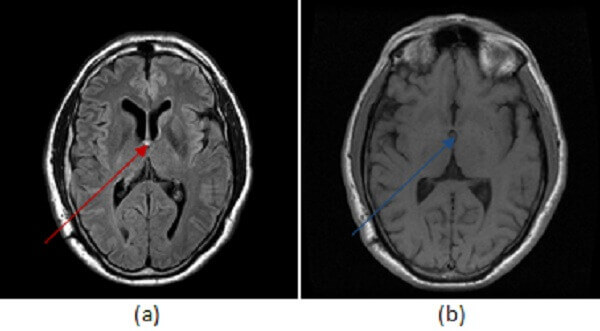

Figure 1: circumscribed FLAIR hyperintense mass at the foramen of Monroe (a, red arrow) is iso to slightly hyperintense to CSF on T1 sequences (b, blue arrow) and does not enhance on post contrast T1 imaging (c, green arrow) .

Colloid cyst is a benign congenital cystic mass that originates from the foregut like other brain cysts (neurenteric and Rathke’s cleft). The mass is typically hyperdense on CT, variable signal on T1 and T2 depending on its water /cholesterol content, nonenhancing and centered in the foramen of Monroe. Although benign, colloid cysts can cause sudden ventricular obstruction leading to rapid onset hydrocephalus and transtentorial herniation resulting in sudden death. Approximately 50% are asymptomatic. Headache is the most common presenting symptom.